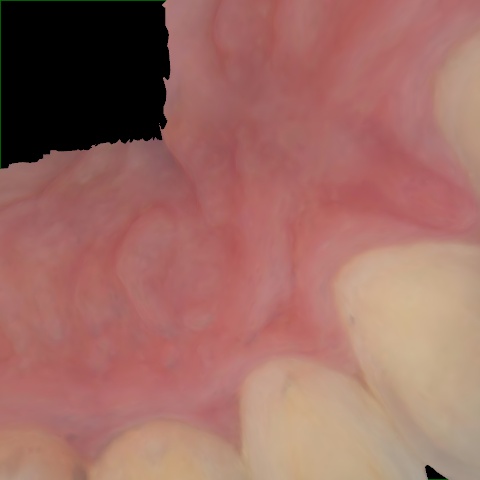

Annotated as "Good"